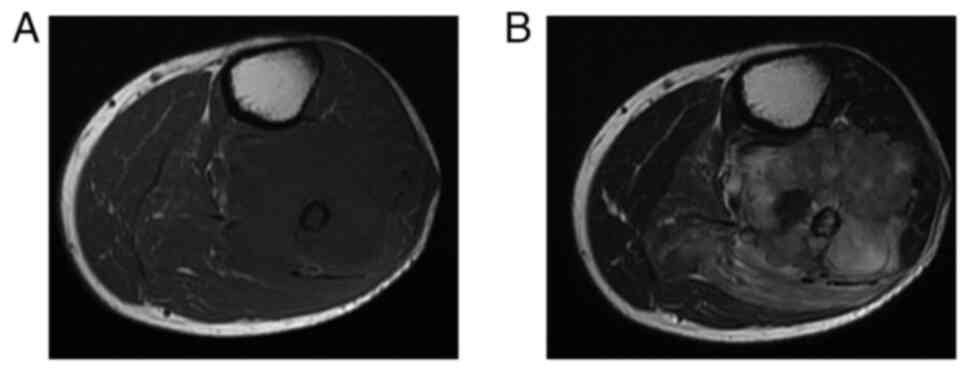

A 64-year-old man was referred to Mie University hospital on October, 2011 due to a mass on the posterior aspect of the left proximal leg. The patient had a history of a Billroth I gastroduodenostomy for a peptic ulcer. A radiograph showed an osteolytic lesion in the left proximal fibula. MRI of the left knee revealed a 6 cm mass around the proximal left fibula (Fig. 6). CT of the head, chest, abdomen, and pelvis did not demonstrate any distant metastases. An incisional biopsy was performed. Histological analysis revealed remarkably polymorphous spindle cell proliferation. Immunohistochemically, the tumor was positive for α-smooth muscle actin, desmin, and caldesmon, but negative for S100, C56, and pan CK (Table I). The aforementioned morphological and immunohistochemical findings were consistent with LMS (Figs. 7A and B, and 8). Neoadjuvant chemotherapy using doxorubicin and ifosfamide was administered. However, the lower leg could not be salvaged due to the diffuse spread to the tibia and popliteal artery. Thus, an above-knee amputation was performed. A total of 2 months after surgery, he developed multiple lung metastases. RFA was performed regularly for the lung metastases. After 1 year, the patient developed a bone metastasis of the left femur, and cryoablation and internal fixation, using a compression hip screw were performed. After 2 years, the patient presented with severe anemia without any gastrointestinal manifestations. CT revealed a protruding mass in the upper part of the stomach (Fig. 9A), and a large pericardial mass with a diameter of 56 mm. Intense FDG uptake in the stomach, left diaphragm, pericardial mass, and paraspinal muscles at the L1 and L4 levels were observed on FDG-Positron emission tomography (Fig. 9B). Cryoablation was performed for the diaphragm metastasis and paraspinal muscle metastasis. Endoscopy revealed a protruding lesion in the anastomotic site of the Billroth I, which was spreading to the jejunum (Fig. 10). The patient underwent combined resection of the stomach and transverse colon. Subsequent histochemical staining confirmed the diagnosis of gastric metastasis from LMS (Fig. 7C).

Figure 6

Magnetic resonance imaging showing a 6 cm mass around the proximal left fibula (A) T1 signal intensity; (B) T2 signal intensity (Case 2).